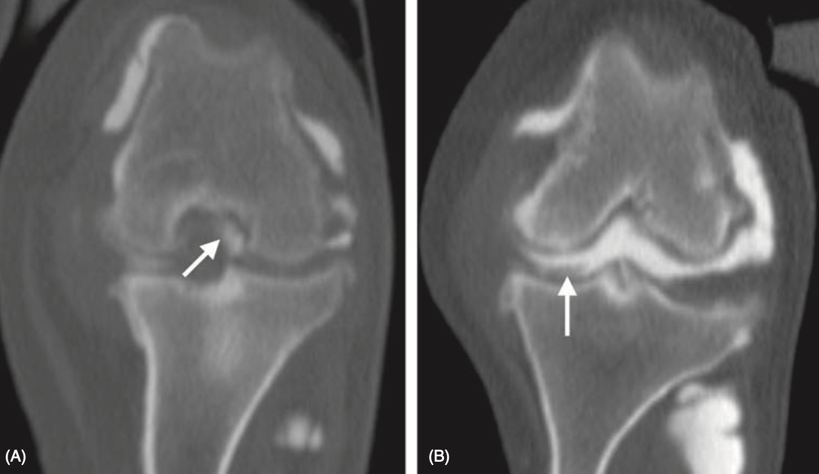

CT má oproti RTG tu výhodu, že umožnuje zobrazit příčné řezy, a proto se při zobrazení nepřekrývají tělní struktury (5). Vyšetření je prováděno v celkové anestezii ve sternální nebo hřbetní poloze. Oba kolenní klouby jsou v extenzi (28). Při poranění měkkých tkáních využíváme jodového kontrastního média, které zvyšuje kontrast a poskytuje větší množství informací o patologii (5). Pomocí CT můžeme detekovat mineralizované tkáně a také časné osteoartritické změny (28).

Obrázek 11: Kolenní kloub v 90° flexi zobrazen pomocí CT, oba kolenní klouby postiženy rupturou LCC, A) přidružen poškozený meniskus v místě, kde se normálně nachází LCC, B) přidružen poškozený meniskus ohraničený kontrastní látkou (2)